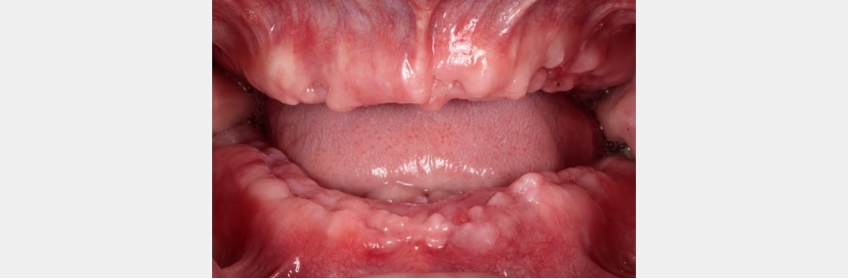

Far less is understood regarding the influence of implant loading protocols when implant overdentures are being utilized. Confusion about appropriate loading times with overdentures is understandable within the context of the risk to osseointegration from micromovement, considering that the implants will be subject to significant loading both under function and when the prosthesis is removed and inserted. The confusion is then amplified when the heterogeneity of overdenture design is considered.

Neither of these papers reported on the influence of the prosthetic design of the mandibular overdentures utilized. Is there a difference in implant success or survival when a passive fitting tissue bar is used rather than resilient individual attachments, like locator or spherical attachments? An article from Elsyad et al. (2021) sheds light on this question by comparing overdentures with immediately loaded implants, “resilient stud” locator attachments, and a bar attachment. In this study, four implants were used in the mandible. At one year, the authors report implant survival as 96.6% for the locator and 98.3% for the passive fitting bar — no statistical difference.